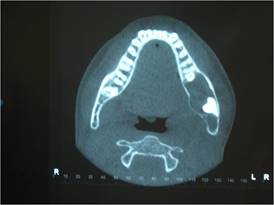

Para una mejor evaluación de la extensión de la lesión, se solicitó una tomografía volumétrica de haz cónico de la región, donde se pudo observar sus límites y relaciones anatómicas circundantes (Fig. 2).